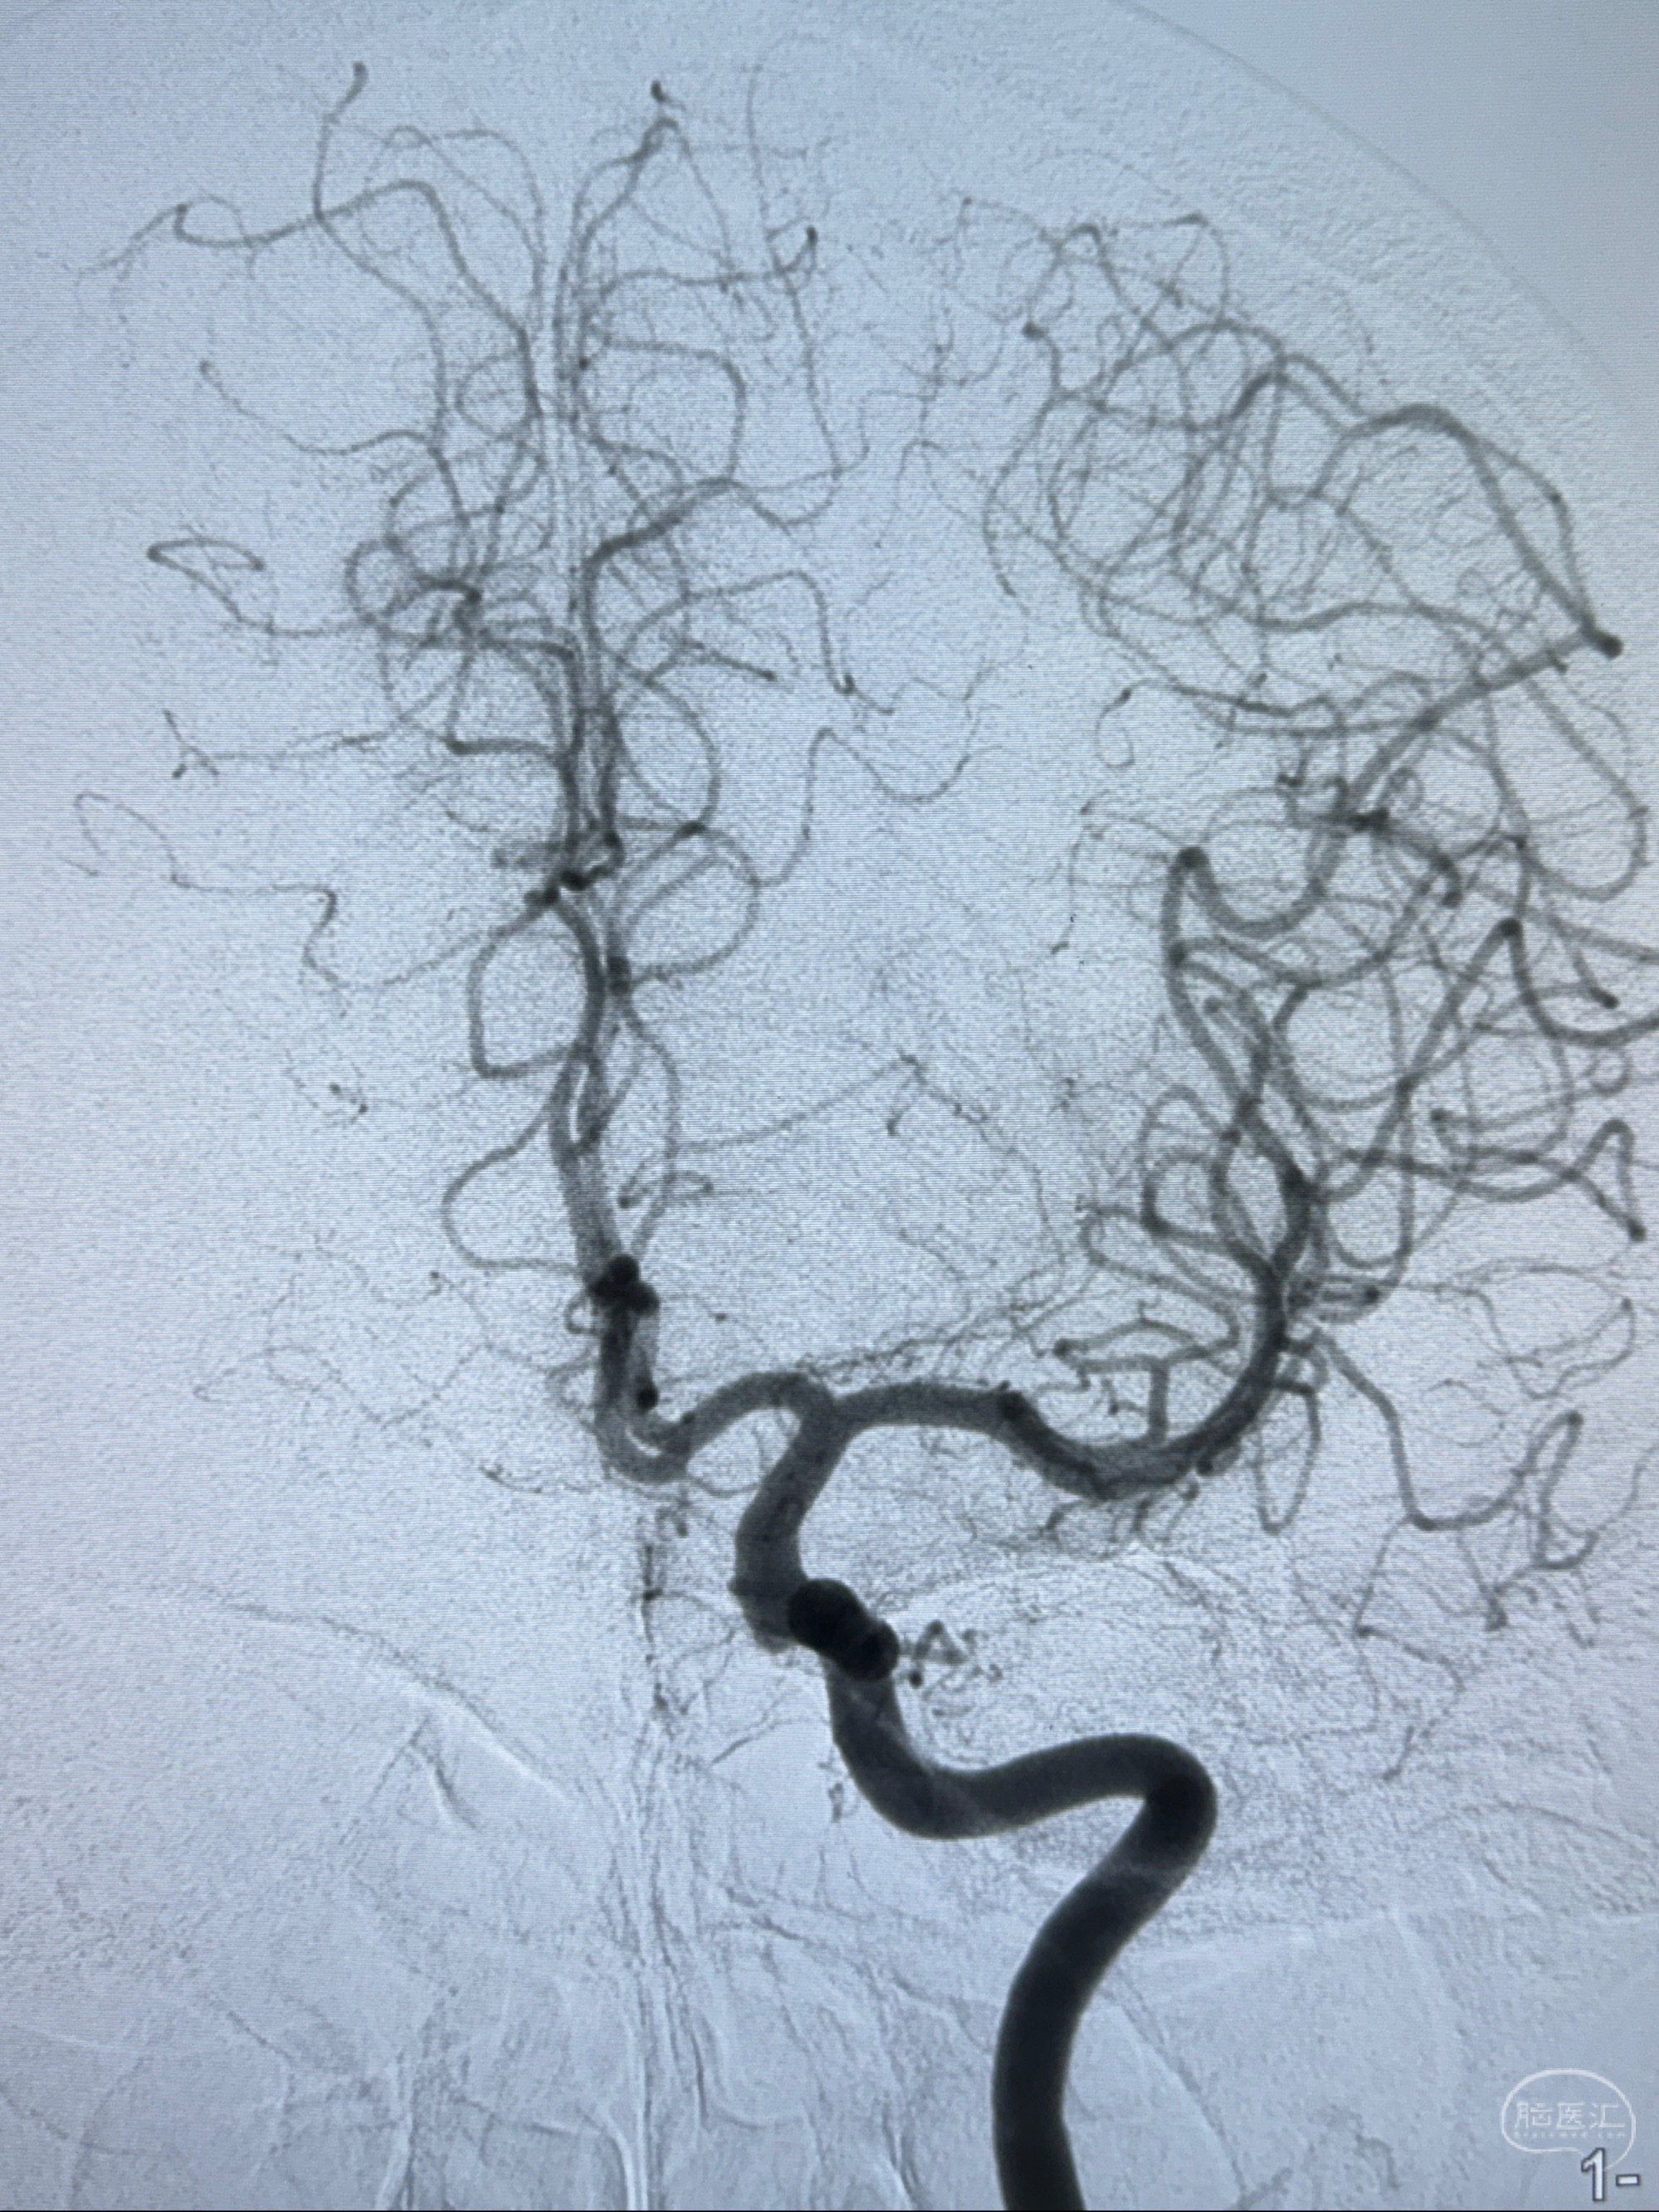

2023-11-01 蓝十字脑科医院 头颅MRI+DWI+MRA:左侧枕叶皮层下小斑片缺血或变性灶,右侧大脑前动脉A1段毛糙,显影淡、纤细,建议完善CTA;

2023-11-03 蓝十字脑科医院 头颅CTA:左侧颈内动脉C6段微小动脉瘤可能(约2mm),右侧大脑前动脉A1段纤细(对侧优势),左侧大脑中动脉提前分叉。

1.左侧颈内动脉瘤

- 随访?

- 支架辅助治疗?